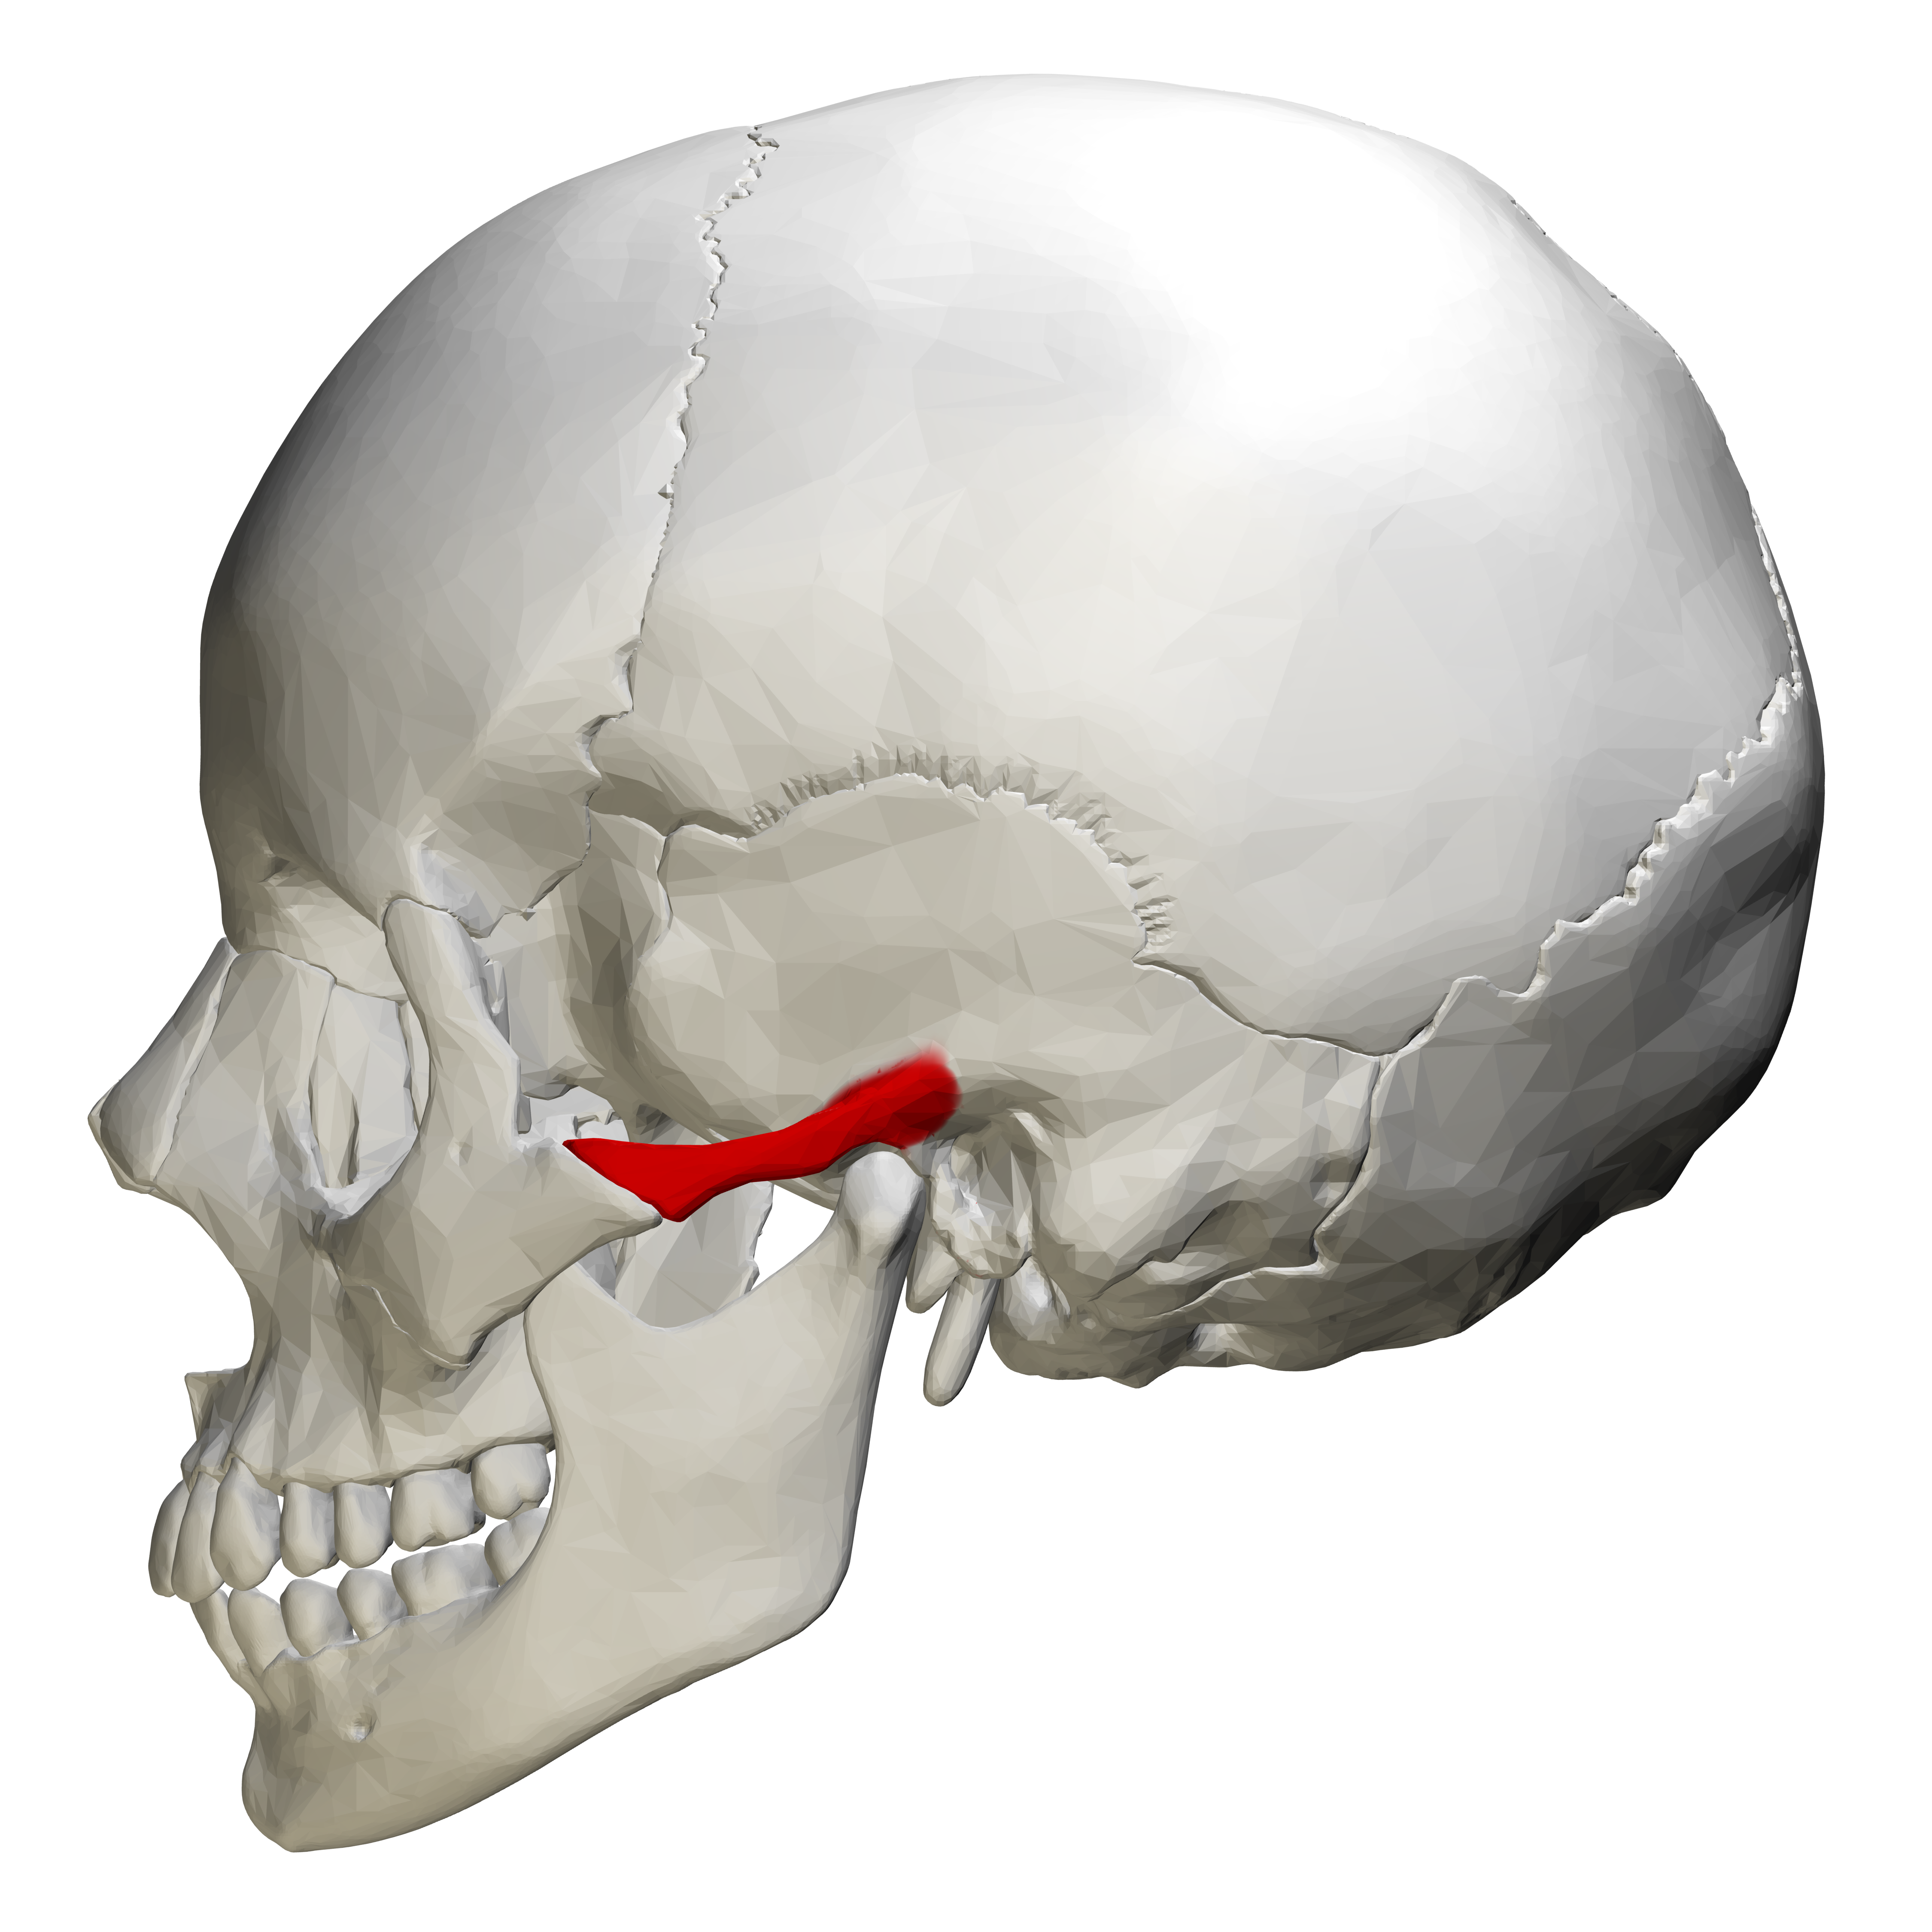

Анатомия сосцевидного отростка